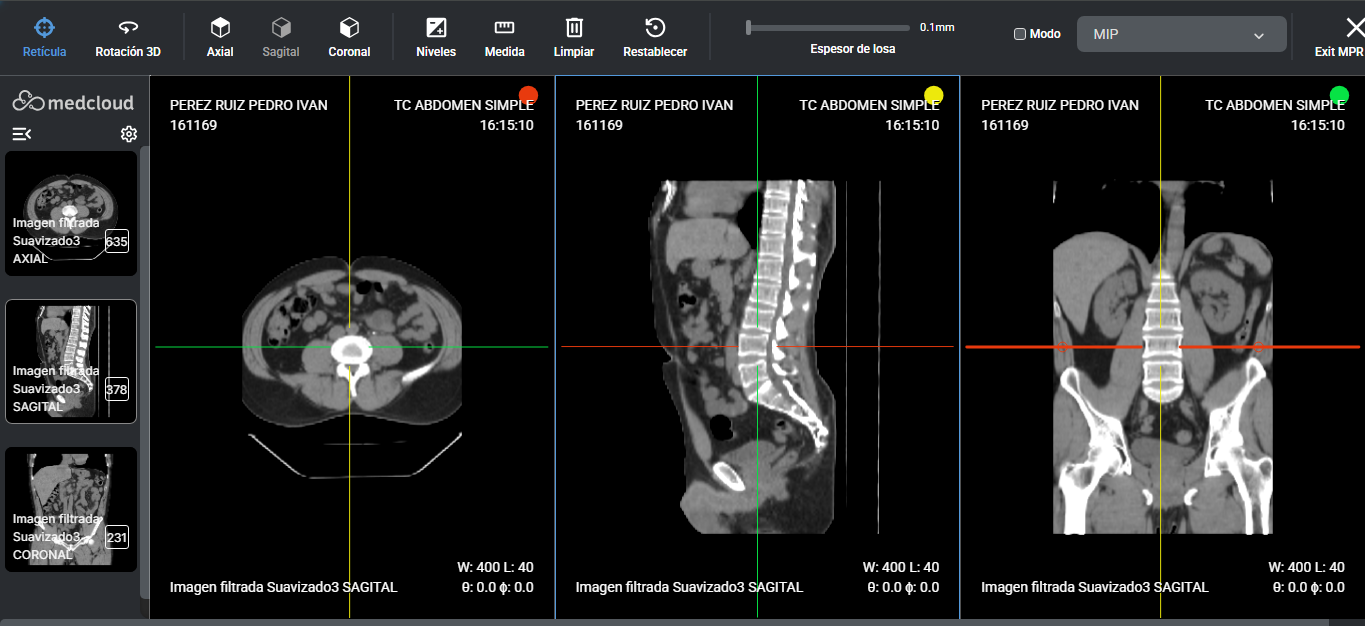

Herramientas con baja curva de aprendizaje. Su equipo se entrenó eficientemente en poco tiempo.

Con sólo unos clics y desde cualquier lugar. Trabajo de calidad y seguro en cualquier navegador de Internet.

Accede a los exámenes desde tu computadora de escritorio o usando tu computadora portátil dondequiera que estés. Acceda a informes, archivos adjuntos e imágenes en calidad original, además de todas las herramientas que necesita, dondequiera que vaya.

Calidad diagnóstica en cualquier lugar, en cualquier momento y en el menor tiempo posible.